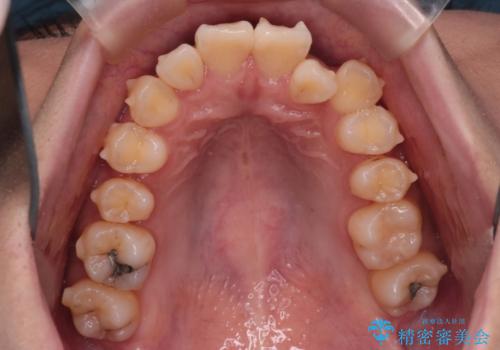

反対咬合を治したい。インビザライン

- 前歯の反対咬合を治したいことを主訴に来院されました。

インビザラインにて臼歯の遠心移動を行いながら、スペースを作り反対咬合を改善することができました。